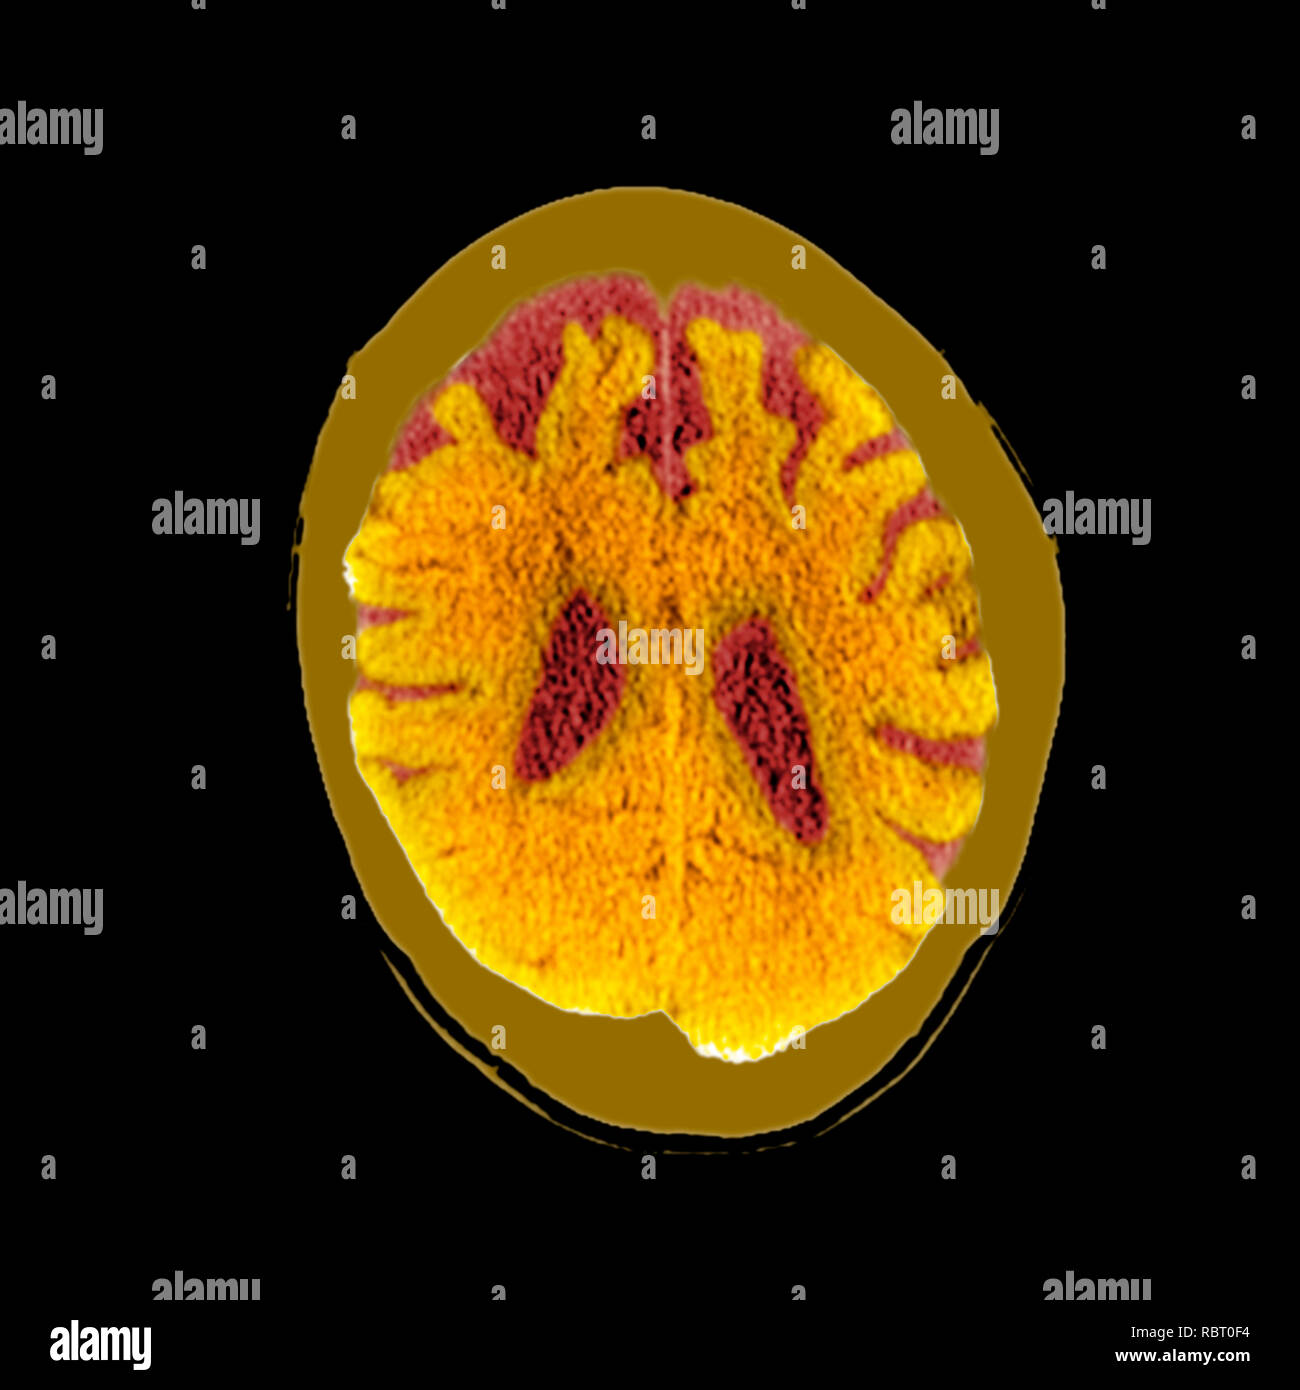

Ct Scan Alzheimer’s Vs Normal – DementiaTalkClub.com

Dementia brain ct hi-res stock photography and images – Alamy

Dementia brain ct hi-res stock photography and images – Alamy